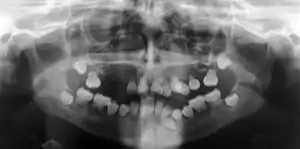

| Preoperative panoramic radiographs showing features of dentin dysplasia type I | |